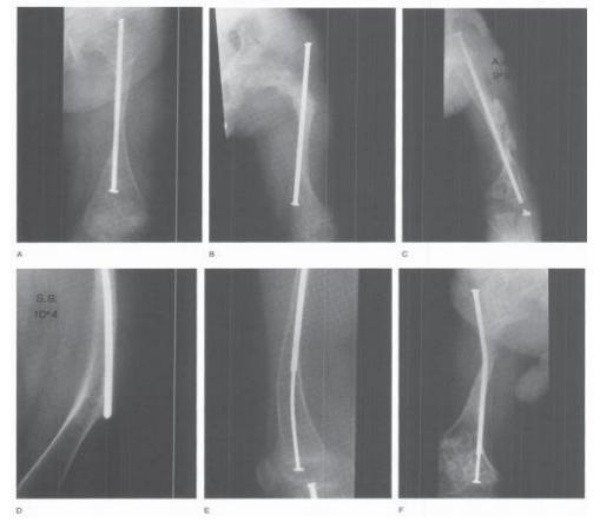

❖ Điều trị gãy xương dài và các biến dạng

- Mục đích: Tái tạo lại trục chi, giảm số lần gãy lại bằng nhiều đường cắt xương và đóng đinh nội tủy (phẫu thuật Miller).

- Chỉ định: biến dạng nặng, giúp bệnh nhân đi lại được.

- Dụng cụ: Đinh không lồng vào nhau (Rush, Williams), đinh lồng vào nhau giúp đinh tự kéo dài khi trẻ lớn (Sheffied rod, Bailey- Dubow rod, Fassier-Duval rod).

Kĩ thuật cắt xương chỉnh trục và đặt đinh nội tủy

Các dụng cụ thường được dùng : (A) Đinh Bailey-Dubow; (B) Bailey-Dubow có chốt ngang đầu dưới (C) Đinh Fassier-Duval (D) dual Rush rods: áp dụng với trường hợp trẻ có xương dài ống tủy rộng, hiện nay chưa thấy biến chứng kiểu chồng nhau bên ngoài của đinh Rush

Kĩ thuật cắt xương chỉnh trục và đóng đinh (đinh Fassier-Duval) mổ mở. Các xương còn lại tương tự.

Các bước chính

- Tiến hành cắt xương tại đầu trên của đoạn cong (A).

- Doa ổng tủy đầu trên của xương để dễ luồn đinh, sau đó doa ổng tủy đầu dưới. Xương thường có ổng tủy lệch tâm, hẹp nên bắt buộc phải doa qua đoạn hẹp nhất và doa đến số thích hợp.

- Lựa chọng đường kính của đinh (đinh to vừa phải để hạn chế di lệch xoay).

- Đặt đầu trên của đinh qua vị trí cắt vào ống tủy sau đó đóng ngược lên qua hố ngón tay (bờ trong mấu chuyển lớn. Gấp háng bệnh nhân để đầu đinh đi ra da gần mấu chuyển lớn (B).

- Dùng tay cầm đinh cầm đầu đinh từ phía mấu chuyển lớn.

- Tiếp tục cắt các đoạn xương phía dưới, số lượng cắt và góc cắt tùy độ mức độ biến dạng.

- Luồn đinh phía trên qua các đoạn xương đã cắt (C).

- Qua đường vào khớp gối, bộc lộ hõm gian lồi cầu đùi.

- Luồn đầu dưới của đinh của hõm gian lồi cầu đùi (D).

- Luồn 2 đầu đinh lồng nhau.

- Tiếp tục luồn để 2 đầu đinh tiến dần vào nhau (đầu trên ở đỉnh hố ngón tay, đầu dưới quay ngang tại hố gian lồi cầu) (E).

- Đóng màng xương, đóng vết mổ theo lớp.

Biến chứng

- 2 đầu đinh không kéo dài ra được do đinh lồng phía trong bị kéo lên trên khi xương dài ra mà do đầu dưới cố định vào xương dưới sụn chưa tốt.

- Đinh trôi vào mô mềm cũng do đầu dưới cố định chưa tốt vào phân xương dưới sụn.

- Đứt đầu dưới của đinh.

- Đầu đinh đâm thủng thành xương.

- Tiêu xương quanh đinh.

- Gãy xương quanh đinh.

- Các biến chứng khác: không liền, nhiễm trùng.